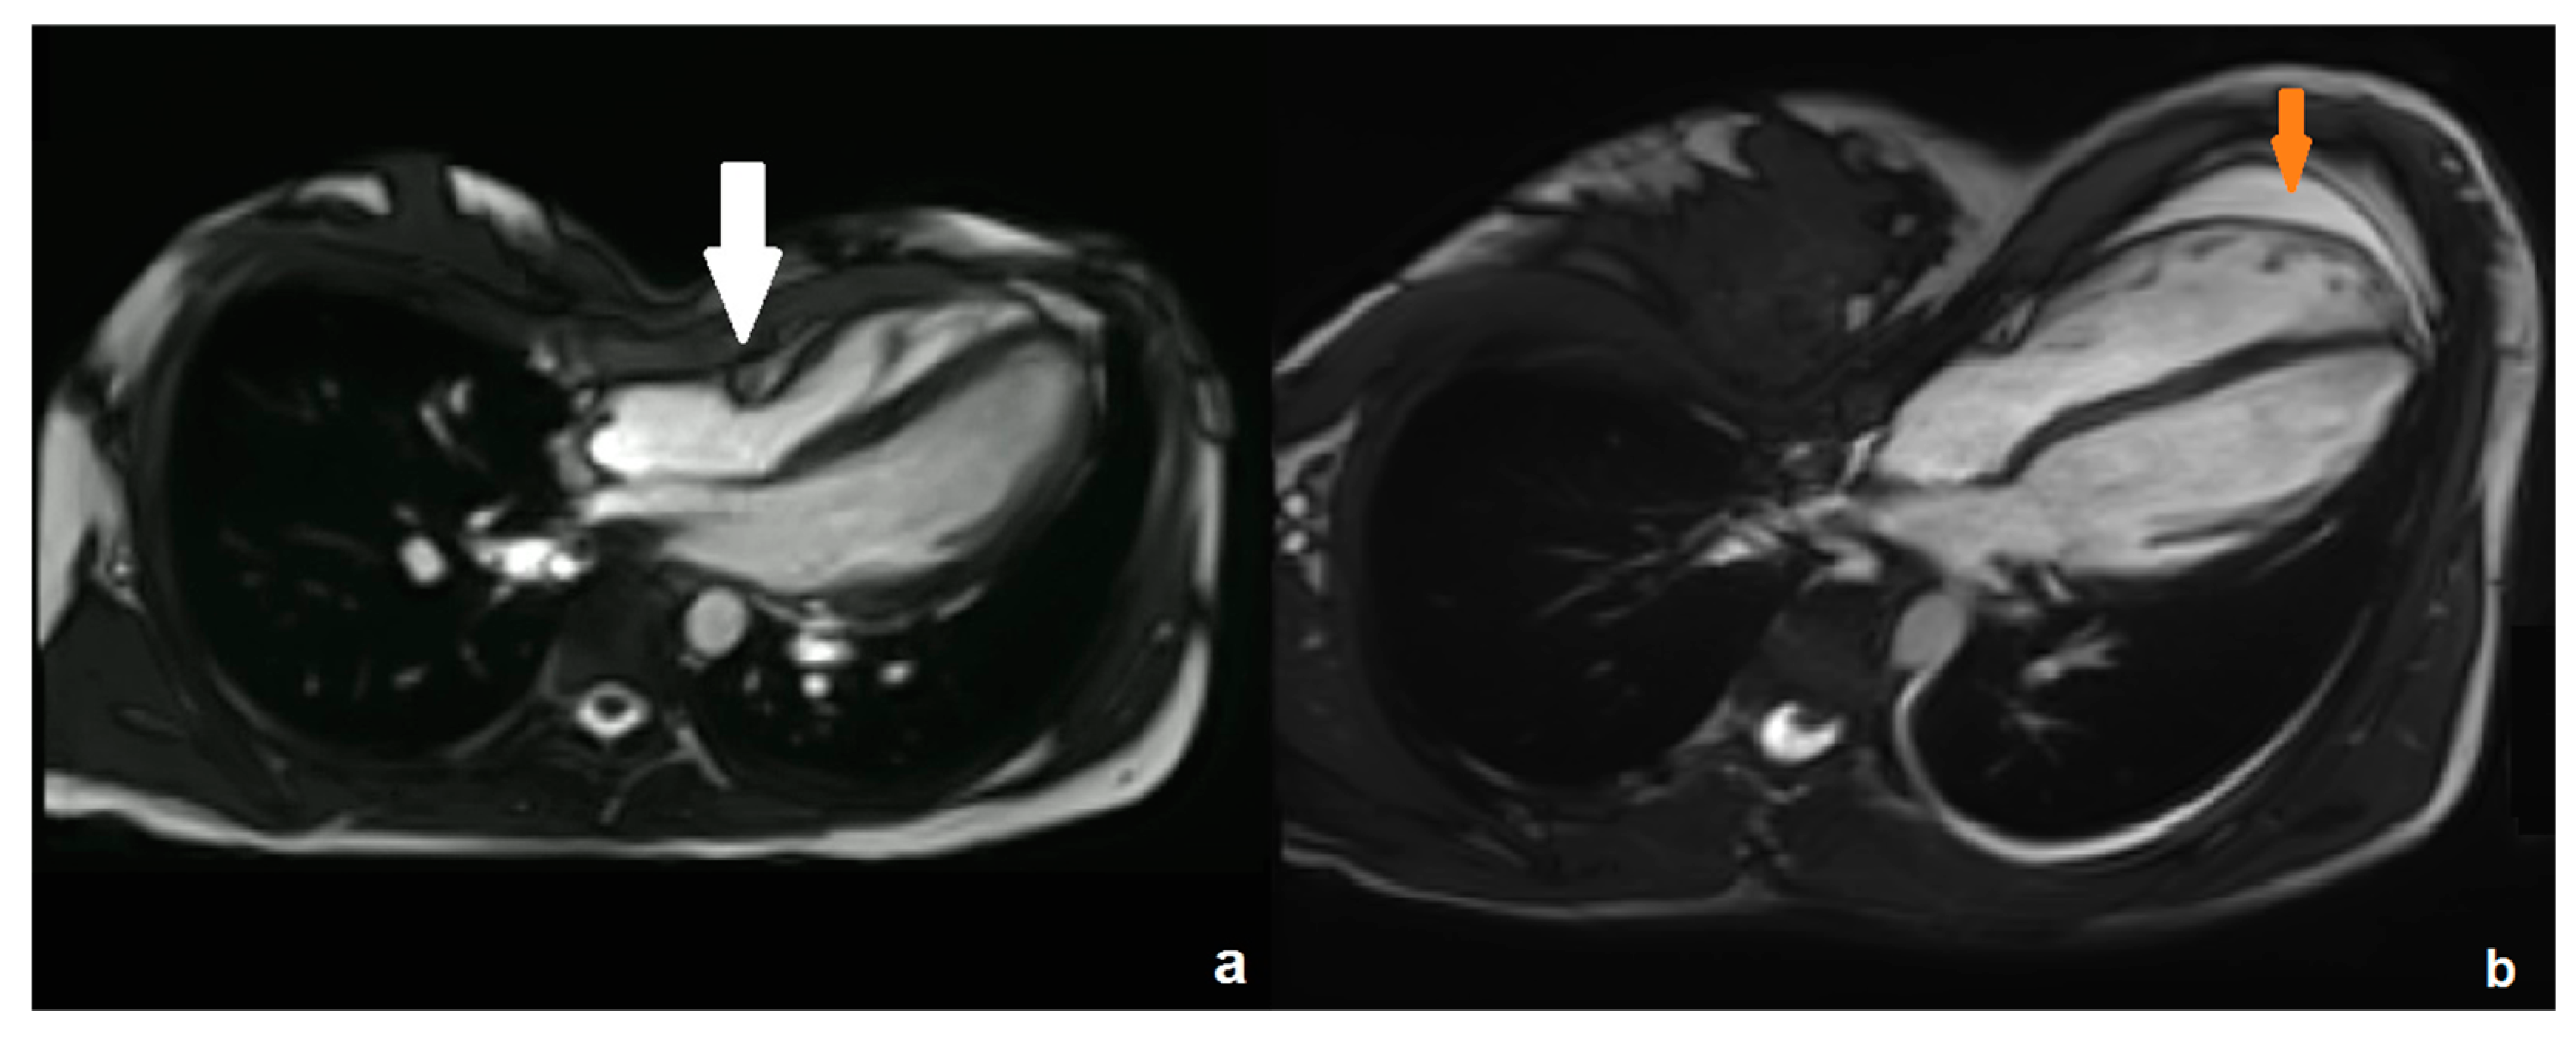

3.1. Cardiac MRI